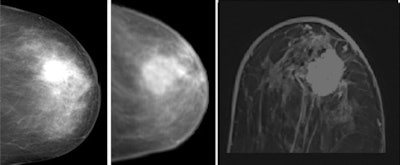

Clinical example of image registration of conventional mammography with high-field MR mammography at 3 tesla. Left, craniocaudal conventional mammography. Middle, virtual craniocaudal mammography. The latter was calculated by the registration software based on the 3D MR mammography dataset. In the image on the right, an exemplary axial view is shown, covering the central part of the advanced enhancing mass (first minute after Gd-DTPA). Histological verification after imaging revealed invasive ductal carcinoma. Images courtesy of Dr. Matthias Dietzel.

Clinical example of image registration of conventional mammography with high-field MR mammography at 3 tesla. Left, craniocaudal conventional mammography. Middle, virtual craniocaudal mammography. The latter was calculated by the registration software based on the 3D MR mammography dataset. In the image on the right, an exemplary axial view is shown, covering the central part of the advanced enhancing mass (first minute after Gd-DTPA). Histological verification after imaging revealed invasive ductal carcinoma. Images courtesy of Dr. Matthias Dietzel.The team matched x-ray mammography and MR-M using a dedicated image registration algorithm that allows semiautomatic nonlinear deformation of MR-M, based on finite-element modeling. To identify registration errors, a virtual craniocaudal 2D mammogram was calculated by the in-house software from MR-M (with and without gadodiamide [Gd]) and matched with corresponding x-ray mammograms. To quantify registration errors, the geometric center of the lesions in the virtual versus conventional mammogram was subtracted. The robustness of registration was quantified by registration of x-ray mammograms to both MR mammograms with and without gadodiamide.